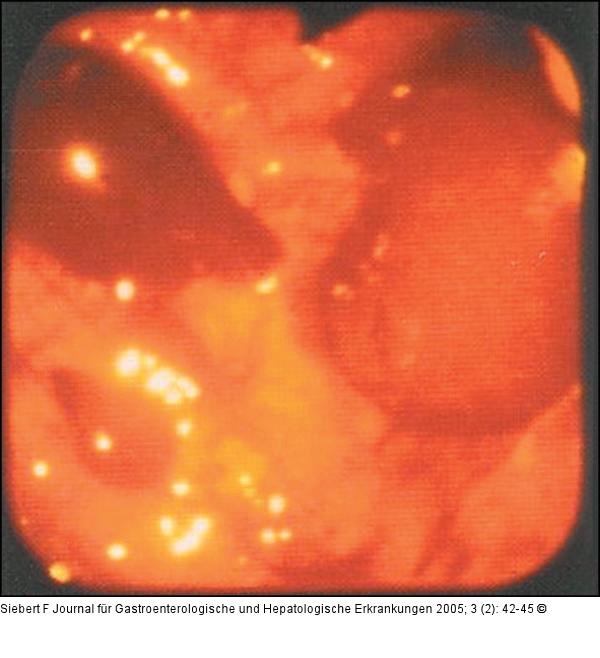

Abbildung 2: Kolon-Ischämie

Kolon-Ischämie – Morphologie, akute Phase